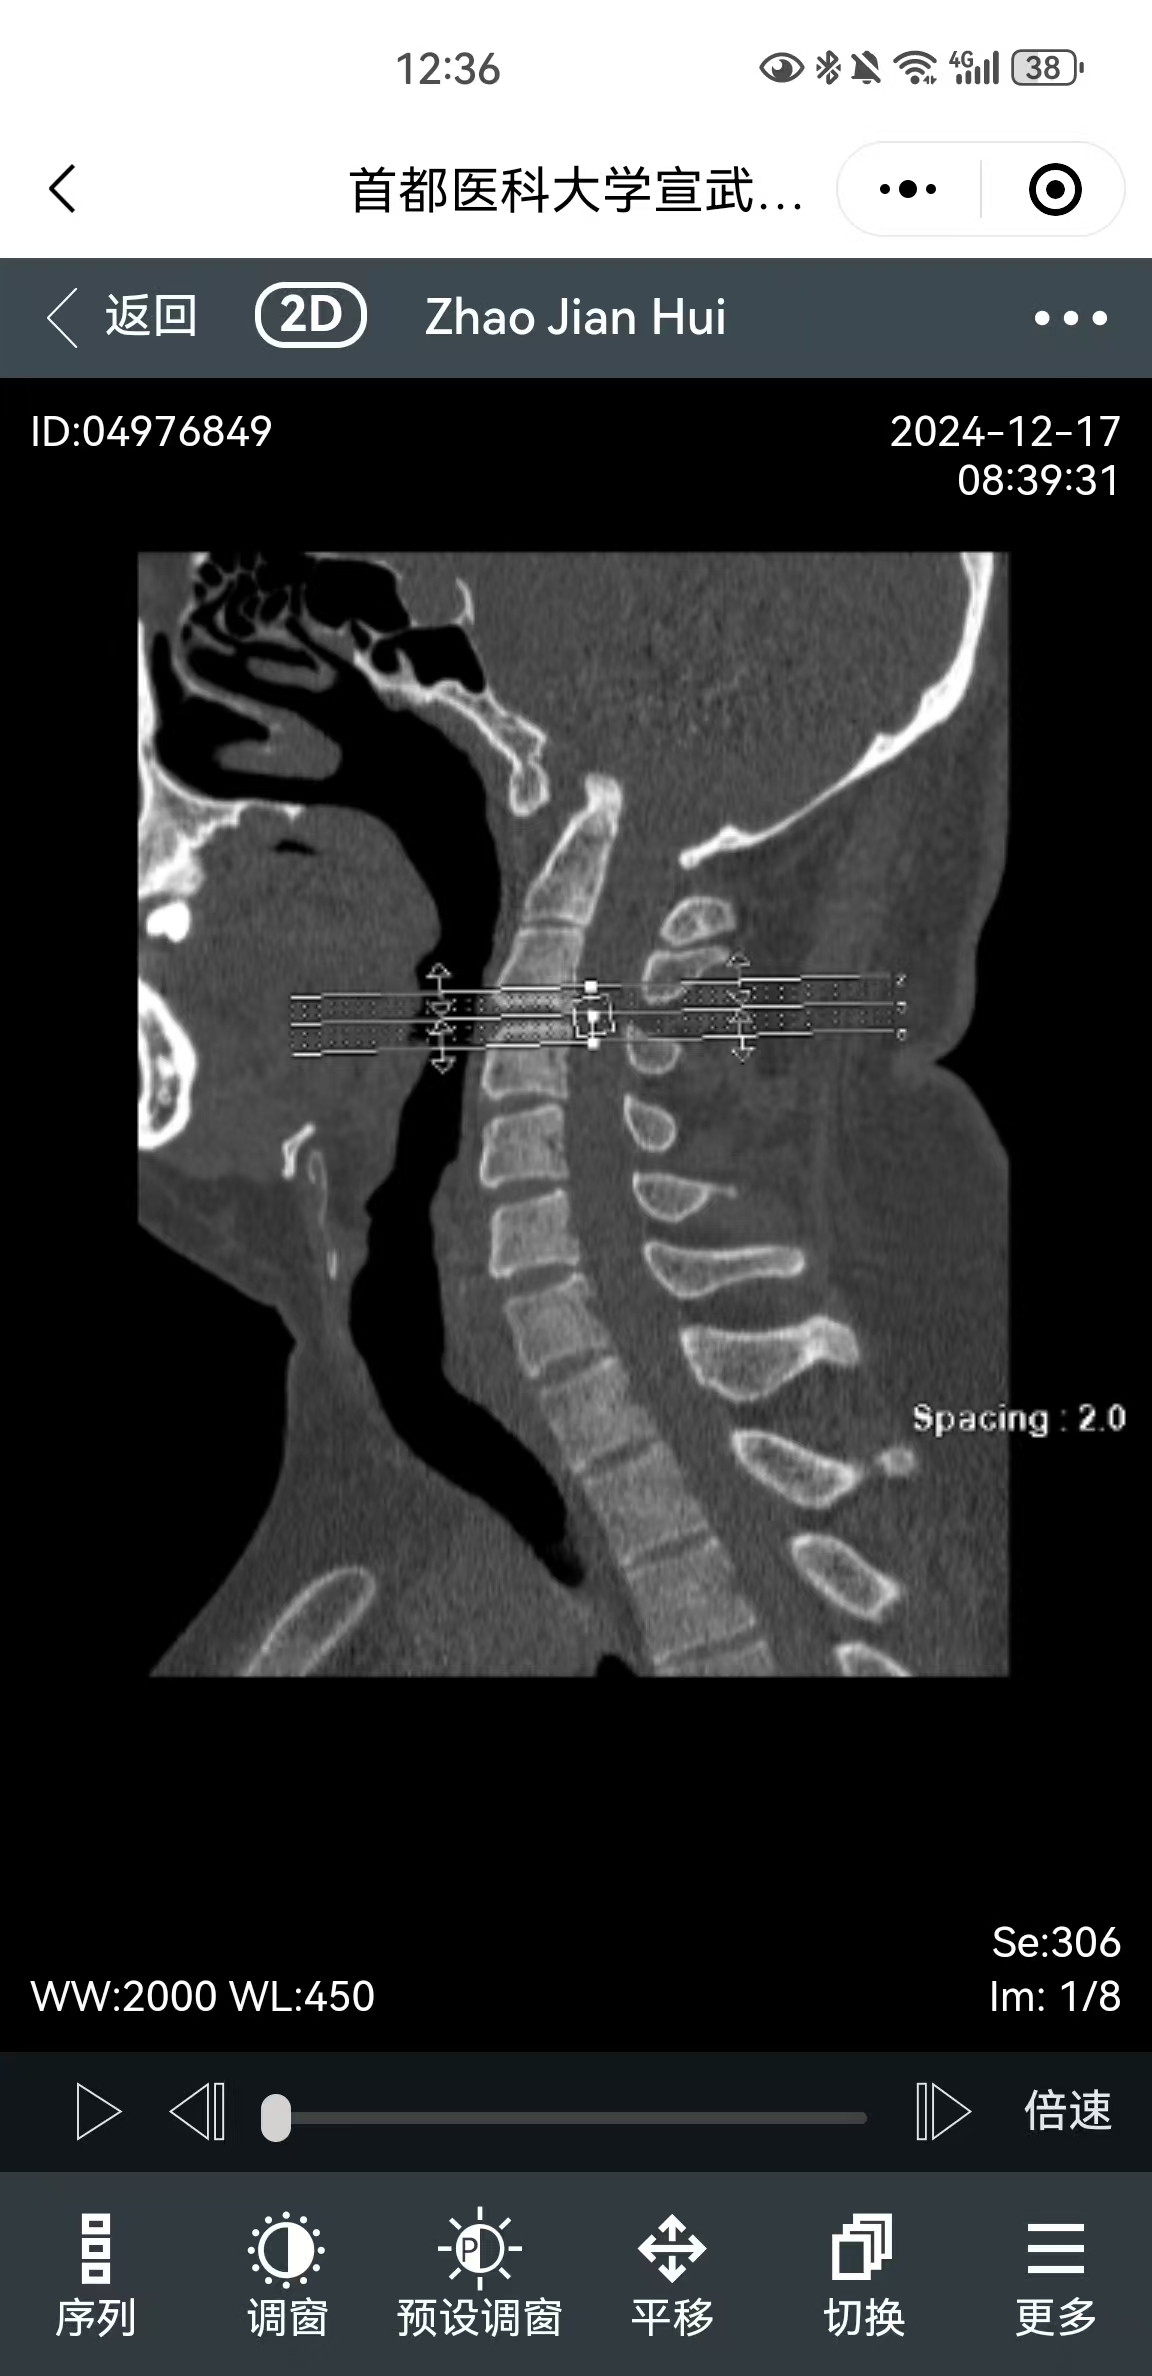

• 影像:

• 术后影像: